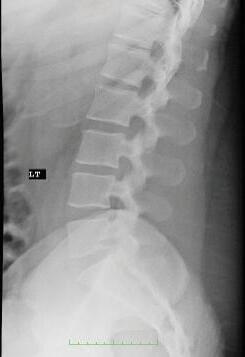

In a lateral projection the path of the x-ray beam is from one side of the patient or body part to the other side. You may hear the phrase “true lateral,” indicating that care was exercised in positioning the path of the x-ray beam in the coronal plane (Fig. 1-5). A “Left” or “Right” side marker is usually placed to indicate which side of the patient was closest to the detector. This is a different use of the markers than in frontal

or oblique projections, in which the markers indicate the right or left side of the patient.

FIGURE 1-5 Left lateral radiograph of the lumbar spine. In lateral views the side indicator (LT) indicates the patient’s side closest to the x-ray detector.